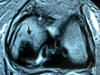

ACT Alteraciones degenerativas en muñeca.

ACT Osteocondritis disecante en art subastragalina. TAC.

ACT Osteonecrosis en astrágalo. TAC.

ACT Osteonecrosis de la cúpula astragalina por afectación vascular.

ACT Osteonecrosis de rodilla, fase 3.

ACT Osteonecrosis de rodilla , fase 2.

ACT Osteonecrosis de rodilla operada con injerto y tornillo.

ACT Osteonecrosis de rodilla. RM.

ACT Osteonecrosis en la cúpula astragalina por afectación vascular. RM.